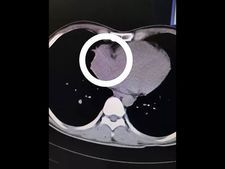

ಕುಡಿದ ಮತ್ತಿನಲ್ಲಿ ಟೂಥ್ ಪಿಕ್ನ್ನೇ ನುಂಗಿದ! ಅದು ಹೃದಯದಲ್ಲಿ ಸಿಲುಕಿತು!